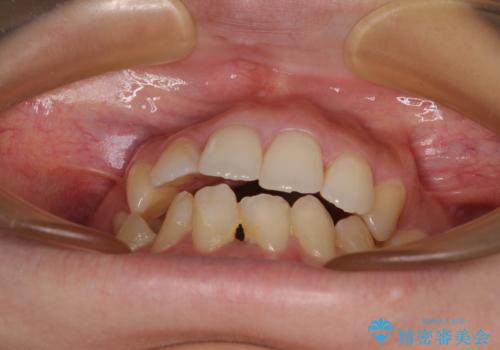

後戻りの再矯正 ワイヤー装置でデコボコと隙間を改善

- 学生時代の抜歯矯正の後戻りが気になり、再矯正を希望して来院された患者様です。

マウスピース矯正は継続する自信がなく、気になるところを短期間で改善したいとのことで、ワイヤー装置にて矯正治療を行うこととしました。

詰め物で隠していた下顎前歯の隙間は、歯軸を改善することで詰め物を除去しても隙間が目立たなくなりました。